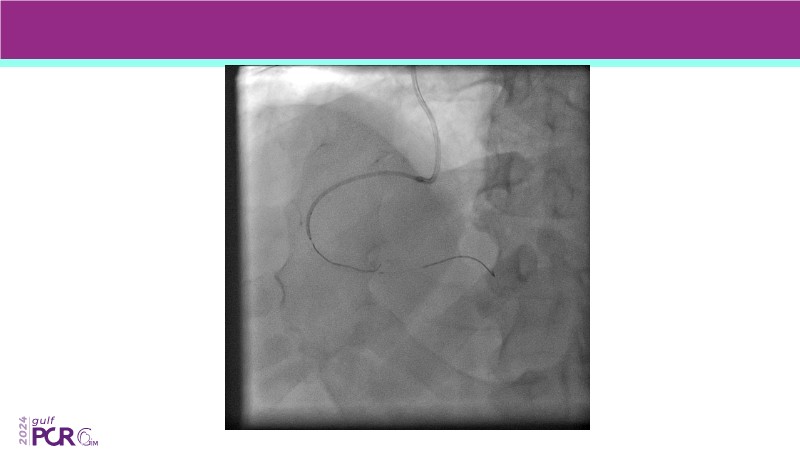

Explore the future of complex PCI with Meril Life’s advanced solutions. Learn about thin-strut platforms, dedicated stents for side branches and diffuse lesions, the role of drug-eluting balloons in metal-free PCI, and the clinical potential of the Myval THV technology.

- To discover your next gen complex PCI toolkit with thin strut platforms and dedicated stenting solutions for managing side branch and long diffused lesions